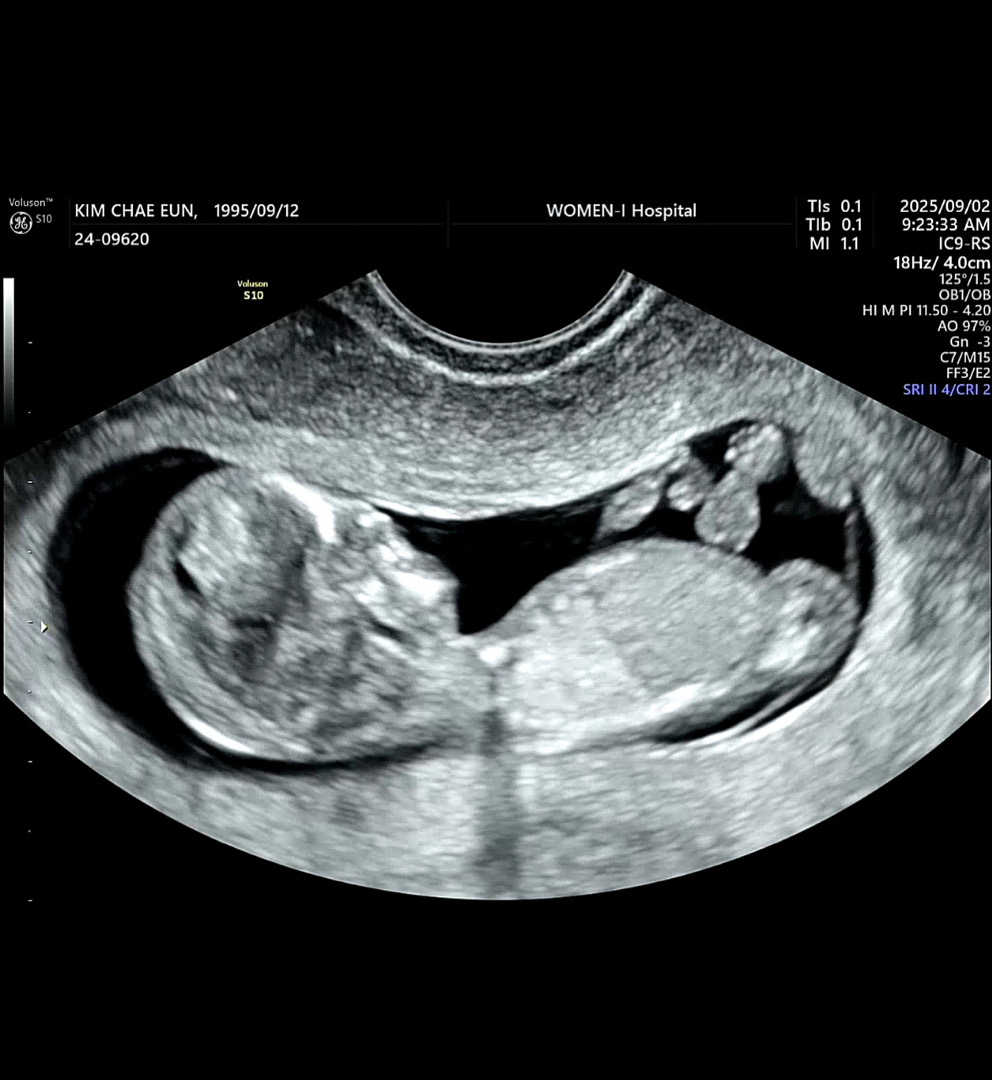

11주3일차 성별예측

지금은 12주3일차고 아기1차기형아 검사갔는데 성별이 궁금하긴한데 각도상으온 아들같네요우ㅜ아들맘 당첨일까요